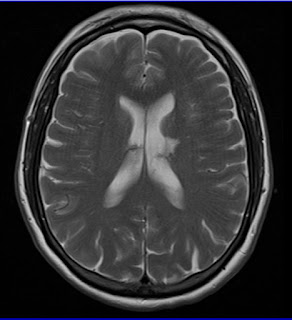

Stroke is a common disease seen by emergency physicians with over 800,000 new cases in the U.S. each year (Mozaffarian, 2016). Both ischemic (embolic or thrombotic) and hemorrhagic stroke patients frequently have derangement of their blood pressure, in addition to the fact that 70% of stroke patients have hypertension as a chronic condition (Miller, 2014). Acute hypertension management has long been a vital component of the medical management of stroke patients. However, guidelines are frequently changing and recent literature has demonstrated that large fluctuations in systolic pressure, whether up or down, lead to adverse outcomes (Anderson, 2013). In this brief review, I want to lay out a framework for dealing with hypertension in stroke patients, based on recent literature and guidelines from the American Stroke Association (ASA).